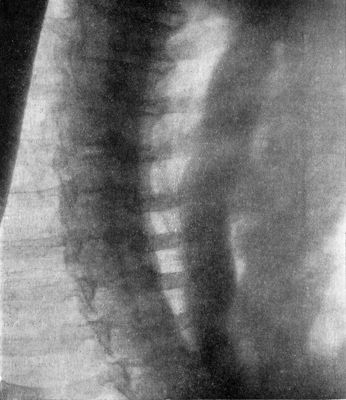

| 212. | Radiogram of Museum Specimen of Pott's Disease in a Child | 435 |